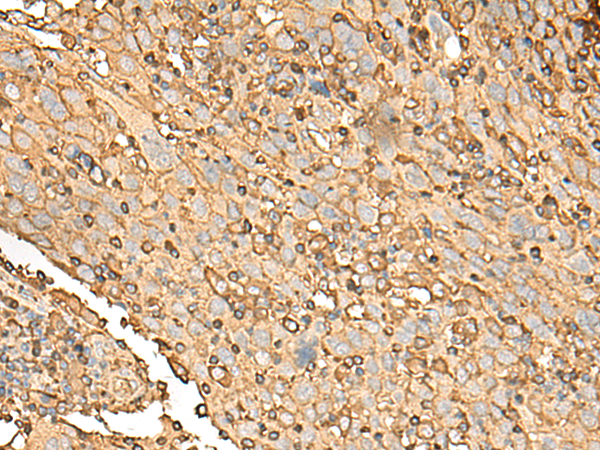

IHC positive control: |

Human cervical cancer and Human colorectal cancer |

IHC Recommend dilution: |

50-300 |